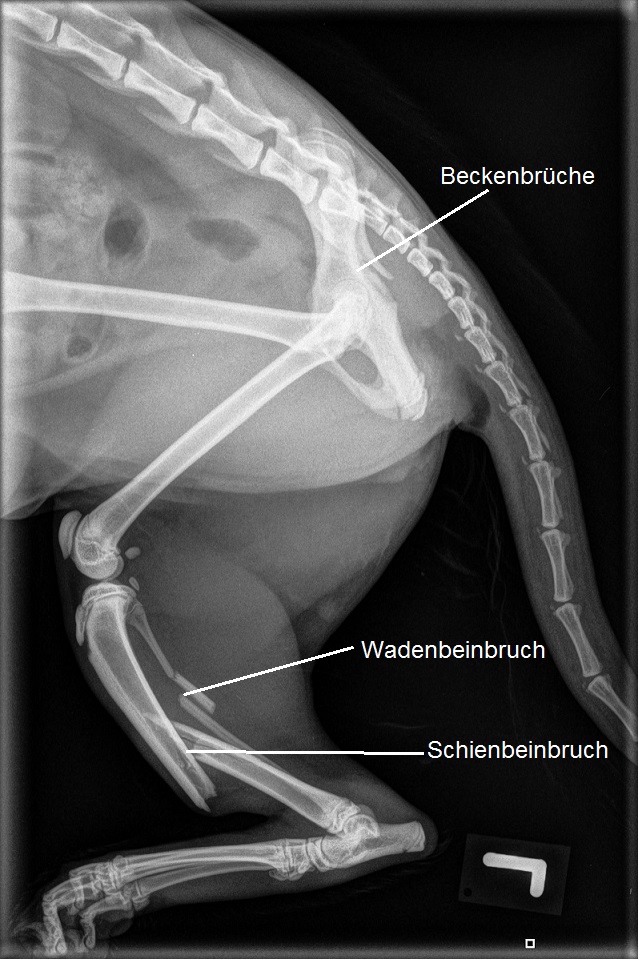

Ada ist apathisch und kann in der Hinterhand nur schlecht stehen, das linke Hinterbein wird komplett entlastet. Im Zuge der Abklärung wird eine Schienbeinfraktur links sowie Beckenfrakturen, Lungenblutungen und ein Lungenriss diagnostiziert.

Ada sollte aufgrund ihrer wohl durch einen Autounfall bedingten Verletzungen umfassend betreut werden: Mit einer intravenösen Infusion muss der Schock bekämpft werden, das Tier müsste auseichend Schmerzmittel erhalten, und nach Abheilung der Lungenverletzungen sollte zumindest der Schienbeinbruch (und idealerweise auch die Beckenfraktur) chirurgisch versorgt werden.

Die Verletzungen von Ada sind allesamt nicht tödlich. In der Regel verheilen Lungenrisse und -blutungen nach einigen Tagen vollständig. Obwohl die Beckenfraktur idealerweise chirurgisch behandelt würde, ist eine konservative Behandlung (Ruhigstellung) bei dieser jungen Katze mit ihrer schnellen Knochenheilung durchaus eine erfolgsversprechende Lösung. Allerdings sollte die Schienbeinfraktur chirurgisch therapiert werden, da eine konservative Behandlung mittels Verbänden wenig erfolgsversprechend ist.